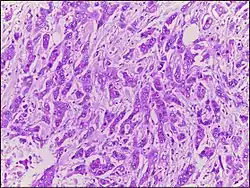

| Micrograph of breast tissue with ductal carcinoma. H&E stain. |

Ductal carcinoma is a type of tumor that primarily presents in the ducts of a gland.[1]